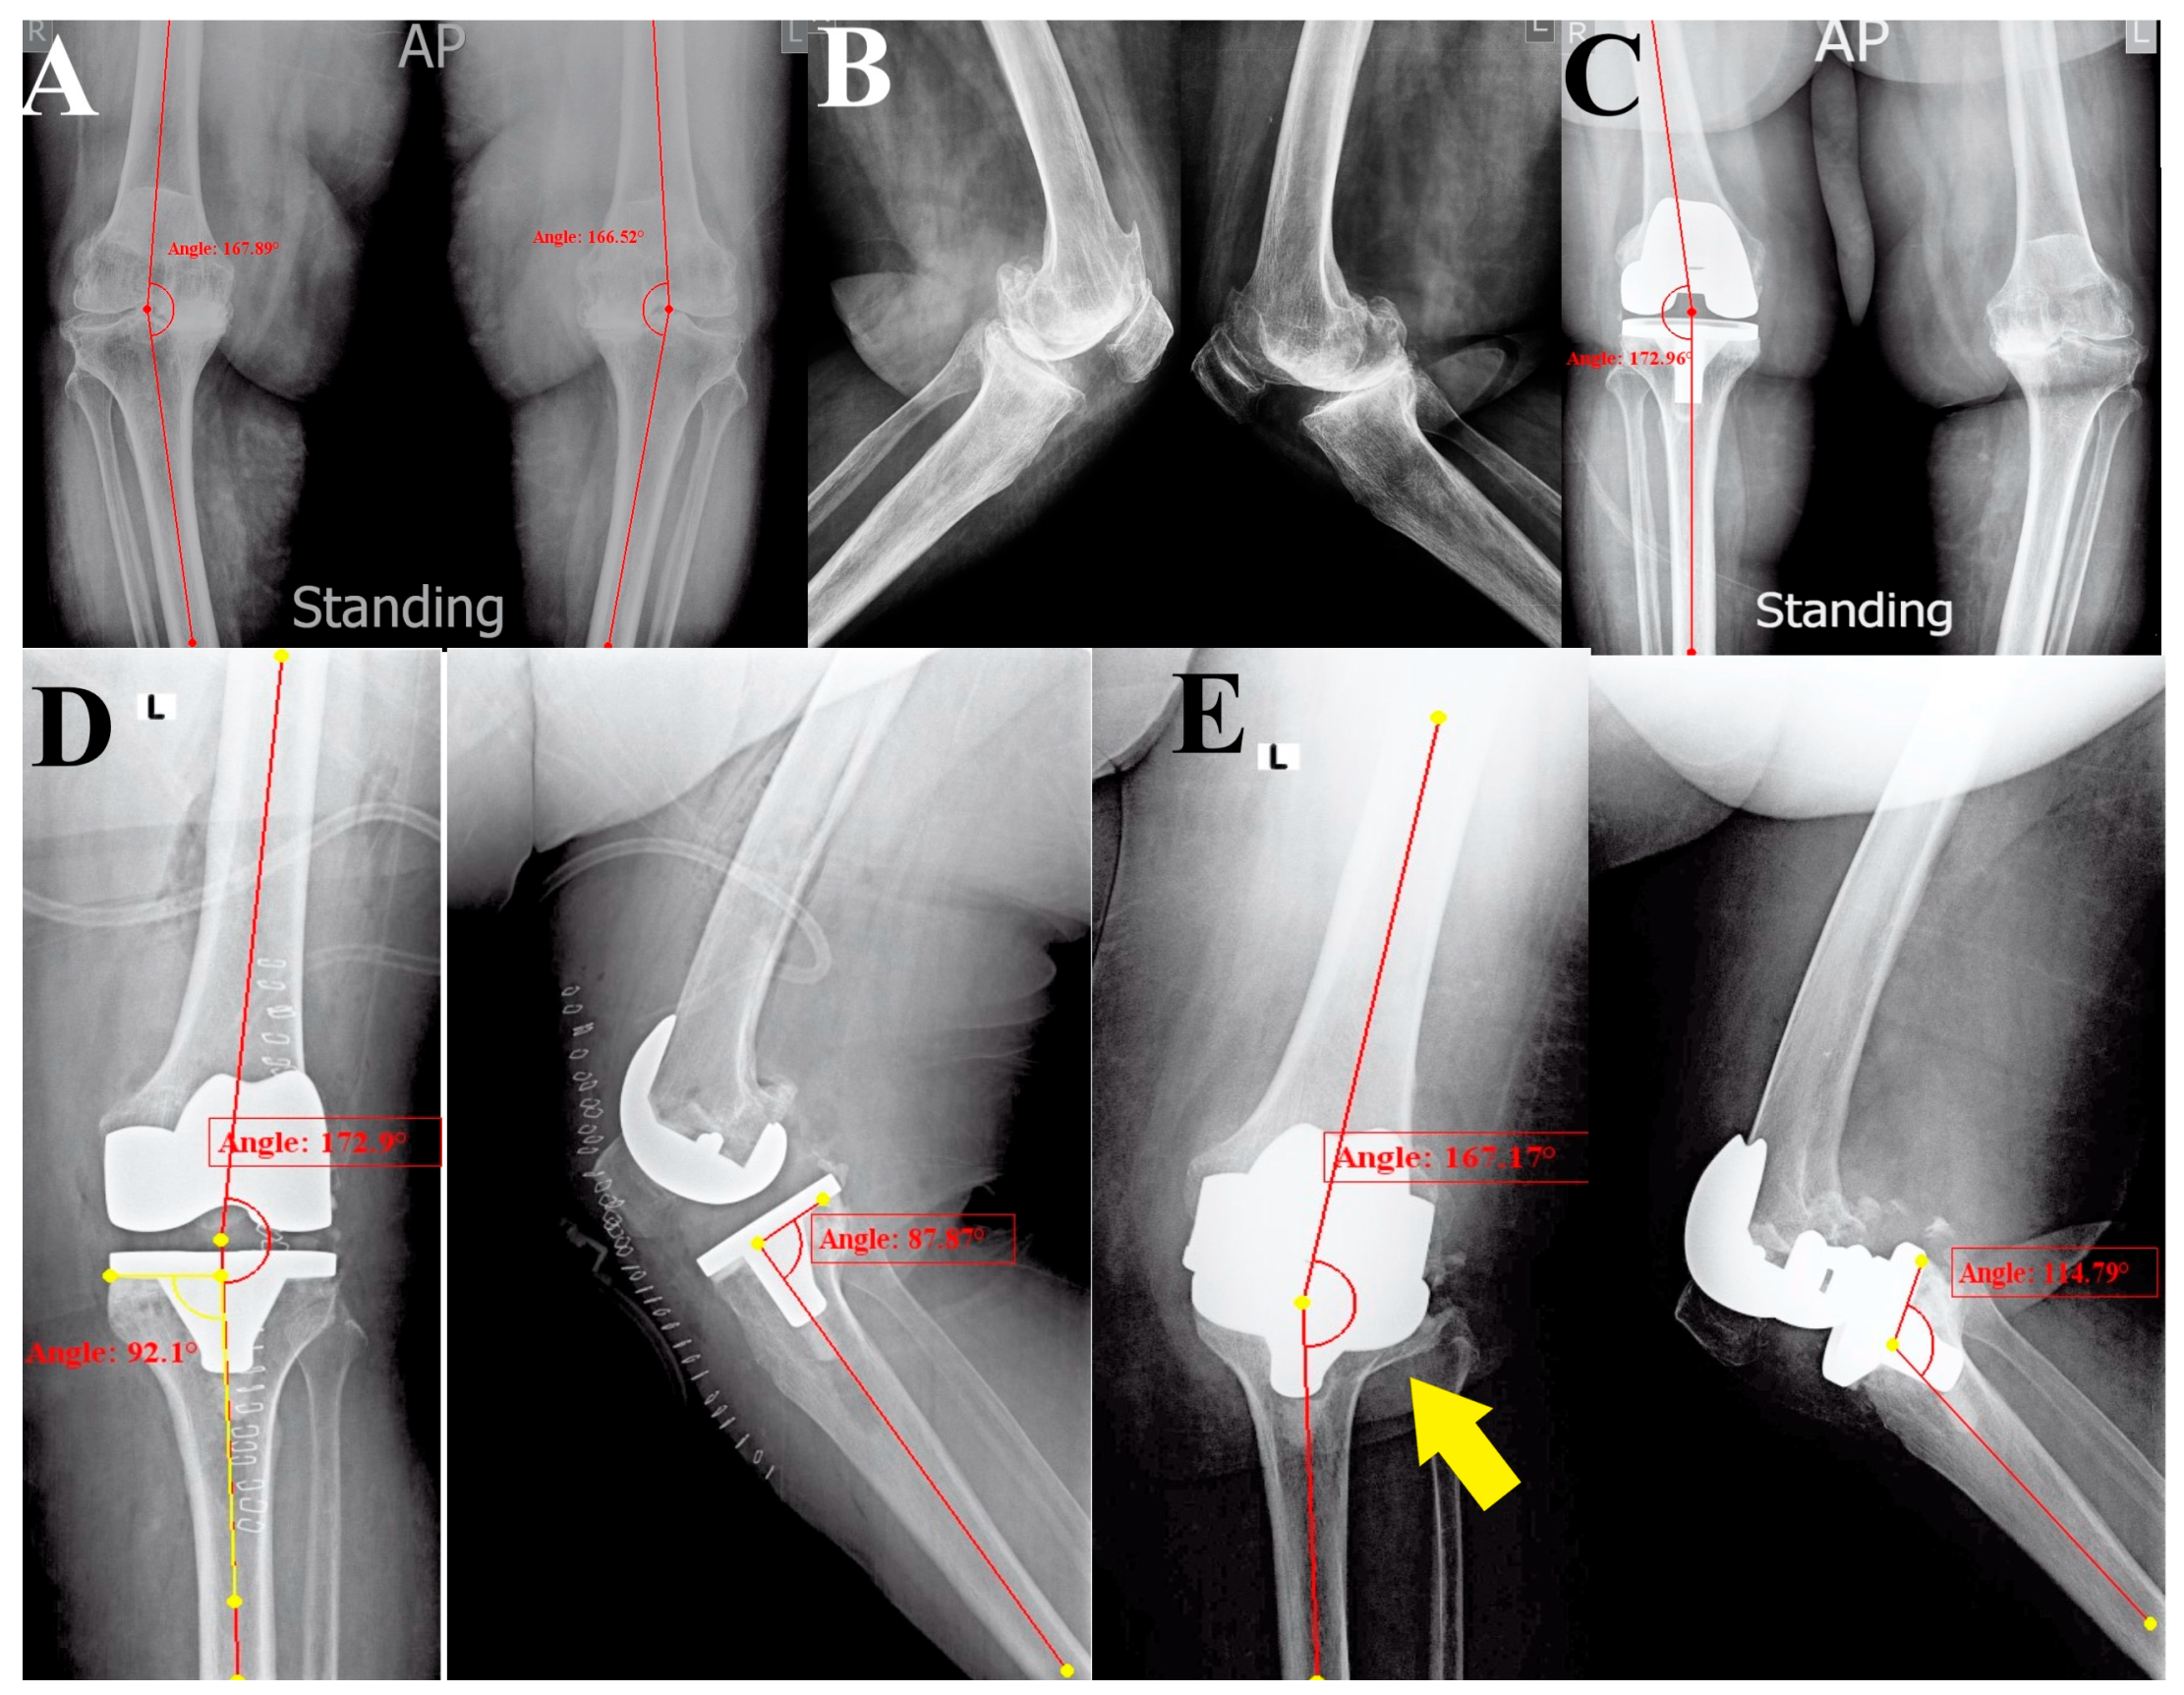

As the clinical picture did not suggest any signs of infection, we decided to manage the patient by revising the TKA (as the fracture was not amenable for fixation and was associated with a loose tibial component), where only the tibial implant would be revised. Examination under anesthesia confirmed the amount of knee instability (Figure 2A). The knee was approached using the same surgical approach as index surgery (medial parapatellar), with careful soft tissue handling. There was a moderate hematoma when opening the knee joint capsule, and the tibial plate was unstable (synovial fluid samples and five tissue samples were obtained from around the tibial component to exclude infection). The femoral component was stable and was protected against scratches throughout the surgery. We carefully tried removing the tibial plate by working on the bone–cement and cement–implant interfaces, especially on the medial side, to avoid further bone loss. After the removal of the tibial implant, the bone defect on the lateral side was evident (Figure 2B), and the fracture of the lateral tibial cortex could be felt, but was not accessible through the approach. The amount of bone loss could be appreciated from the cancellous bone attached to the lateral side of the removed tibial baseplate undersurface (Figure 2C). Reconstruction was performed using a stemmed tibial baseplate and two metal wedges to compensate for the lateral tibial defect (Figure 2D,E). The lateral tibial cortex fracture was ignored.

Figure 2. Intraoperative demonstration. (A) The gross valgus alignment of the left lower limb. (B) The knee was approached using the same approach as for the primary TKA (medial parapatellar); the femoral component was retained, and after removing the tibial implant, the defect of the lateral tibial plateau was evident (blue arrows). (C) The removed tibial implant showed bone attached to the lateral side (yellow arrow), indicating the fractured lateral tibial plateau. (D) The revision stemmed the tibial implant with two wedges (red arrows) to reconstruct the lateral tibial plateau bone defect. (E) The lateral tibial plateau cortex fracture was ignored (as it was inaccessible through the approach), and the final tibial component was implanted.